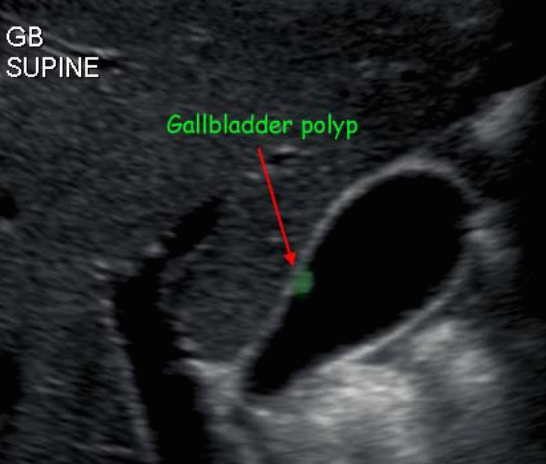

담낭 용종 ( GB polyp ) 담낭 안쪽 벽에서 담낭 안으로 돌출된 다양한 형태의 점막이 두꺼워진 것이다. 용종 자체로는 큰 문제를 일으키지 않으나, 용종의 크기가 커지면 암으로 변할 가능성이 높다. 용종의 크기가 직경 10mm 이상인경우 악성일 가능성이 높다.

1. 콜레스테롤 용종 (cholesterol polyp) : 50~90%로 가장 흔한 타입

- 1cm 미만의 고에코의 종괴 (hyperechoic mass) : 담석에 비해 에코가 낮고, 담낭벽보다는 고에코로 보임

- 담낭벽에 붙어 체위변화 시 이동이 없다

- 후방음영이 없다